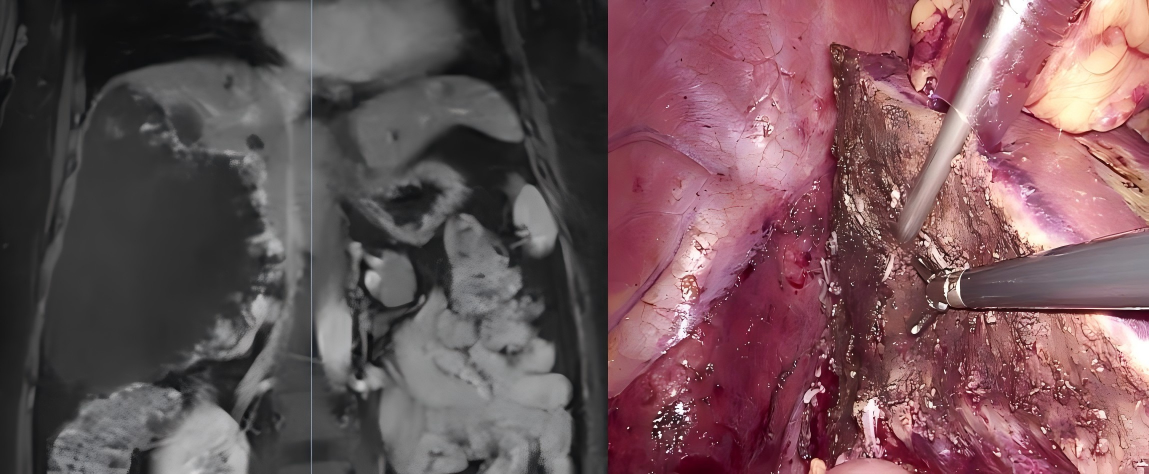

患者为中年女性,因腹胀入院。完善影像学检查,确诊为右肝巨大血管瘤,瘤体最大径约18cm,占据整个右肝,且与右侧肝蒂、肝右静脉及下腔静脉关系紧密,手术操作空间狭小,病变显露与切除难度极大,对手术操作提出了较高要求。

刘锋主任医师团队采用3D 4K荧光腹腔镜开展手术。术中循Laennec膜解剖显露右肝肝蒂,明确左右半肝分界线;通过外周注入吲哚氰绿,沿荧光染色界面离断肝脏实质,逐步显露肝中静脉。待肝脏断面充分展开后,离断右肝肝蒂,以下腔静脉前方为背侧切缘标识,离断腔旁肝实质,充分显露并离断肝右静脉,使右肝达到完全无血流状态,最后离断肝周韧带,完整切除肿瘤。该术式最大程度避免了传统术式先期游离肝周韧带、显露肿瘤引发的大出血风险。手术最后延长脐下小切口,将标本置于取物袋内剪碎后取出。